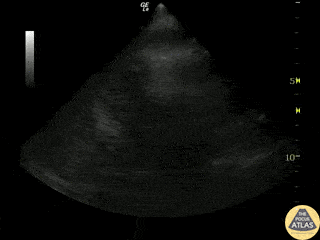

No free fluid is seen between the spleen and the diaphragm. Dr. Justin Bowra